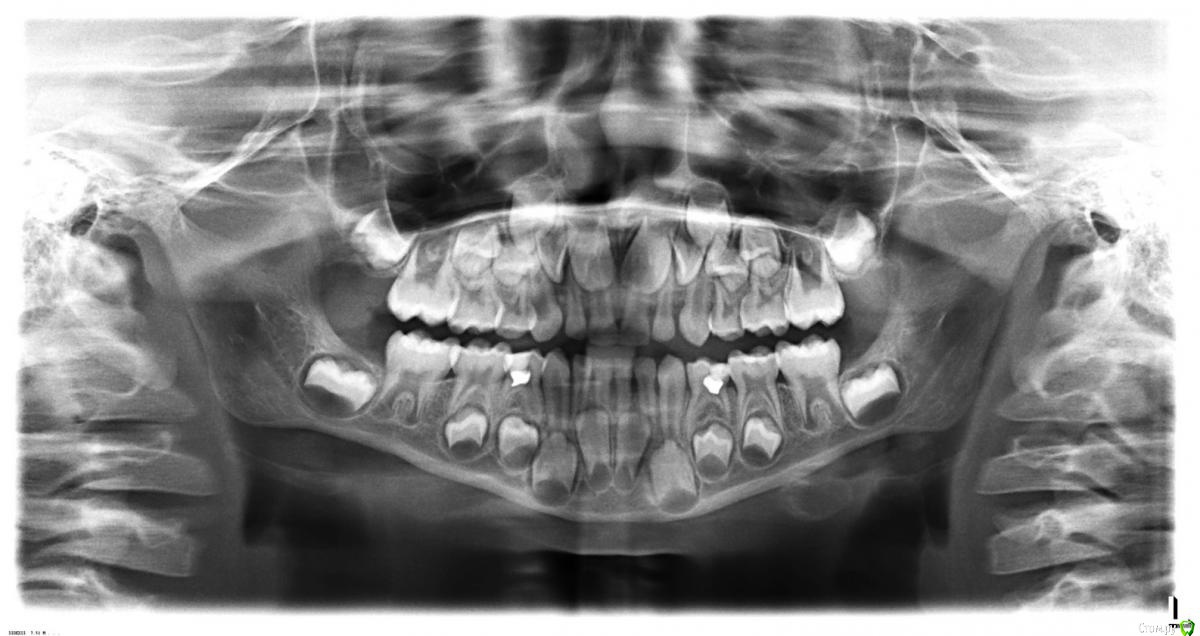

ЛенаАлександровна Опубликовано 1 января, 2016 Поделиться Опубликовано 1 января, 2016 (изменено) Здравствуйте!Помогите,пожалуйста,советом.Забыла указать в названии.Криво стоят на снимке постоянные.Молочные зубки ровные.Прорезывались вовремя и в правильном порядке.Если я правильно понимаю,то верхние двойки стоят боком.Их придется разворачивать какой-нибудь пластиной,когда прорежутся.Или они могут сами еще при прорезовании нормально встать? Касательно нижних.И в детской теме,и на консультации мне подтвердили,что это не центральные резцы,а двойки.Поэтому и смена задерживается.Снимок сделан летом.По сей день ситуация та же.Молочные все на месте.Про 8ки не сказали ничего.Они еще могут появиться или их тоже можно отнести к адентии? На сегодня обошла всех ортодонтов,кого знала,как хороших в нашем городе.Сказали ждать смены.Это,действительно,так?Или быть может как-то надо подготовить процесс смены?Есть же случаи,когда удаляют молочные зубки,чтобы постоянные нормально росли.Может,моему сыну тоже что-то такое необходимо,а я сижу время теряю? Заранее спасибо. Изменено 1 января, 2016 пользователем ЛенаАлександровна Ссылка на комментарий

Yana guapa Опубликовано 2 января, 2016 Поделиться Опубликовано 2 января, 2016 1. сделайте фото зубов2. Про восьмерки рано еще говорить3. Центральные или боковые резцы- не столь важно в такой ситуации4. Если судить по снимку- то молочные зубы стоят слишком плотно. В таком возрасте в норме между зубами должны быть щели (тремы). Челюсть должна расти, должно появляться место для постоянных зубов, которые значительно крупнее молочных. Чаще всего молочные зубы так плотно стоят у детей, которые мало получают грубой пищи (яблоко, морковь, мясо, сухари, баранки... Ничего не измельчать, не тереть). От нагрузки челюсти растут, нет нагрузки- челюсти не растут. 5. Удалять ни в коем случае ничего нельзя. Каждый молочный зуб бережет место доя постоянного, передает нагрузко на кость, чтобы челюсть развивалась... [font=helvetica ... Или быть может как-то надо подготовить процесс смены?Есть же случаи,когда удаляют молочные зубки,чтобы постоянные нормально росли[/font] 1 Ссылка на комментарий

Yana guapa Опубликовано 2 января, 2016 Поделиться Опубликовано 2 января, 2016 Перекрытие нормальное. Трем и физиологической стираемости , конечно, совсем нет(( прикус соответствует ~4годам. Рекомендации пока что теже, грызите!))) 1 Ссылка на комментарий

Yana guapa Опубликовано 2 января, 2016 Поделиться Опубликовано 2 января, 2016 Скажите,пожалуйста,а чем чревато такое отствание в прикусе на 3 года?Мальчику восьмой год идет.. Дефицитом места для постоянных зубов, скученностью. Нуа вообще, надо смотреть на ребенка в целом - на сколько он отличается (или не отличается от сверстников)? Размер челюстей, носа, работа мышц, функции дыхания, глотания, жевания, речеобразования.... всё это влияет на лицевой скелет, его гармоничность и тд 1 Ссылка на комментарий